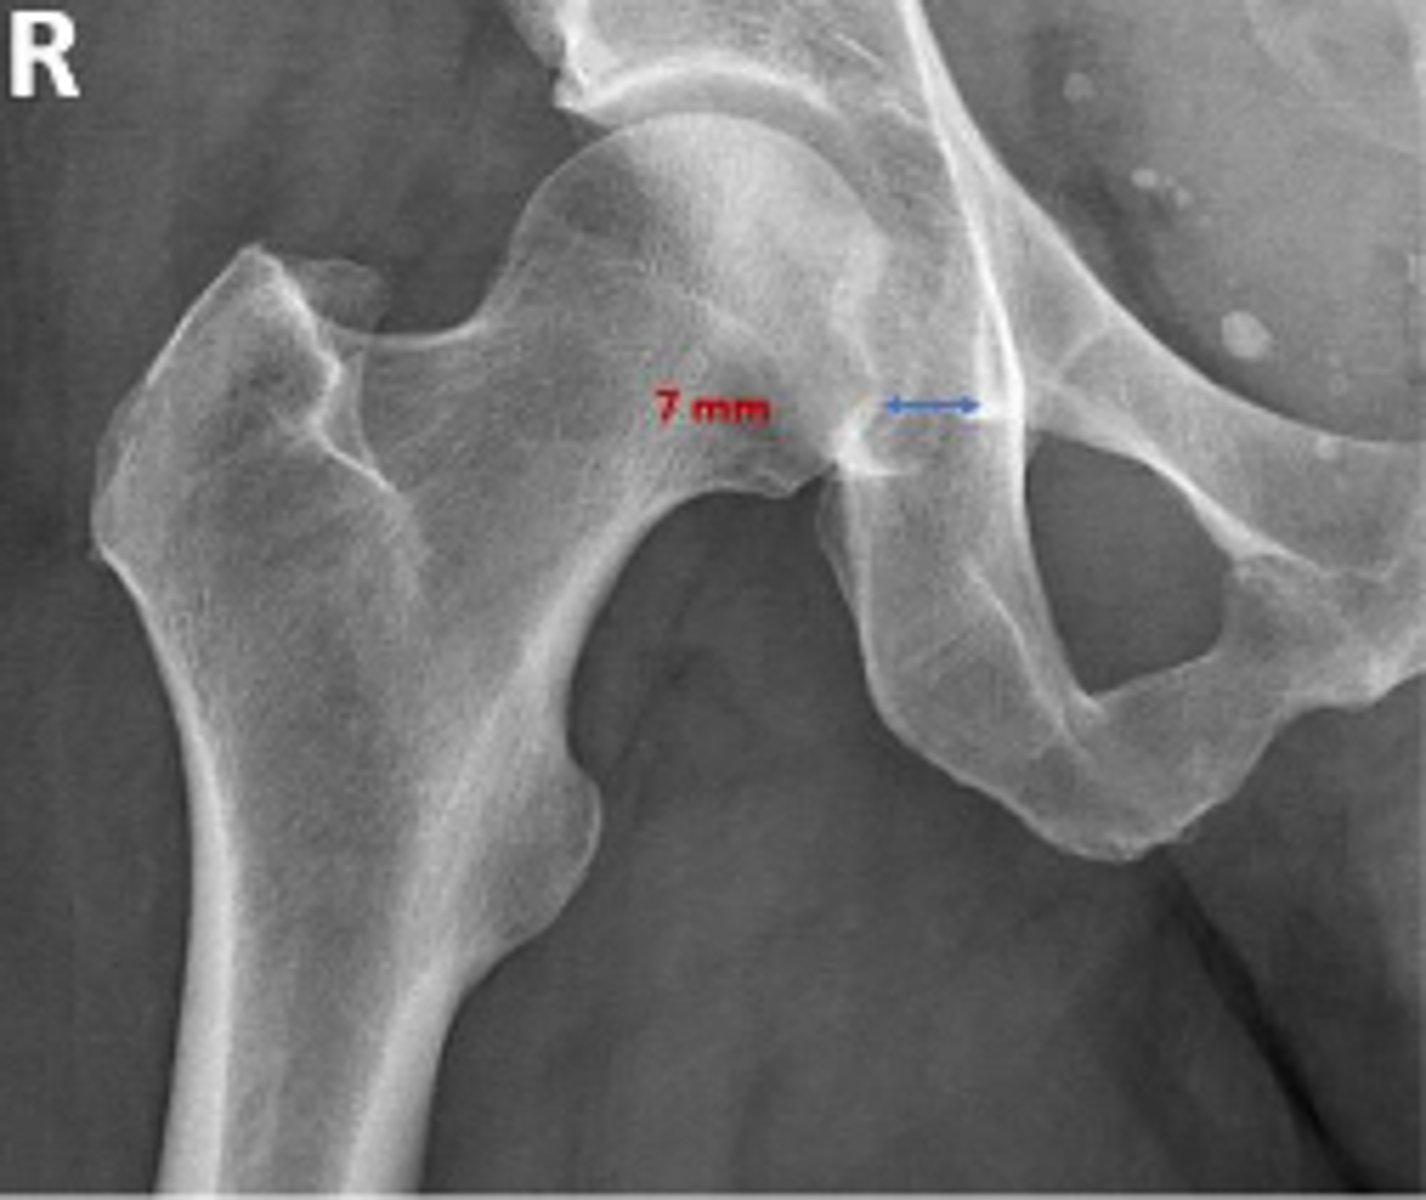

AP right hip

What is the radiographic view?

Teardrop distance

What is the name of the assessment?

6-11mm

What is the normal range for this assessment?

The distance between the most medial margin of

the femoral head and the adjacent pelvic

teardrop

What are the osseous landmarks for this assessment?

Yes (normal is 6-11mm)

Is the measurement within normal limits?

Femoroacetabular joint inflammation

Name 1 condition that may result in a measurement of 15mm?

AP pelvis and AP hip views

Name 2 radiographic views for this assessment?

Late stage degenerative joint disease

Protrusio acetabuli

Name 2 conditions that may result in a measurement of 3mm?

Waldenstrom's sign

What is the named sign if this assessment has a value > 2mm difference

between the left and right side?